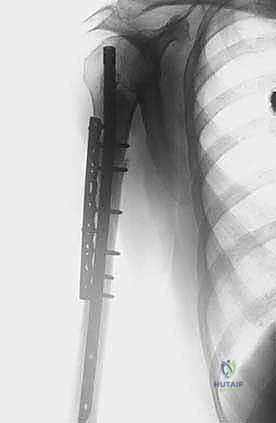

* المسمار النخاعي التشابكي (Intramedullary Nailing): يتم إدخال سيخ معدني قوي من التيتانيوم داخل التجويف النخاعي لعظم العضد بالكامل، وتثبيته بمسامير عرضية من الأعلى والأسفل. هذه الطريقة توفر دعماً ميكانيكياً هائلاً للعظم، وتمنع الكسر، وتسمح للمريض باستخدام ذراعه فوراً.

* غالباً ما يتم إجراء هذه الجراحة بتدخل محدود (Minimally Invasive) باستخدام أجهزة التنظير الإشعاعي (C-arm) داخل غرفة العمليات لضمان الدقة المطلوبة دون الحاجة لشق جراحي كبير.

إعادة البناء الميكانيكي: يتم إدخال المكونات المعدنية (سواء مسمار نخاعي، شرائح، أو مفصل صناعي) وتثبيتها بقوة باستخدام الإسمنت العظمي إذا لزم الأمر. يتم التأكد من ثبات الهيكل الجديد تحت جهاز الأشعة السينية المباشر (C-arm).